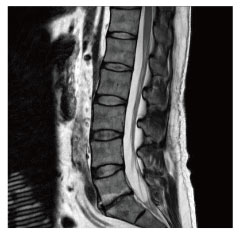

当院のMRI画像集